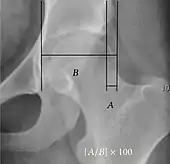

| Reimer's migration index[9] | ![]() |

The percentage of the femoral head that lies outside of the acetabular roof. It is also called the femoral extrusion index. | <25% |